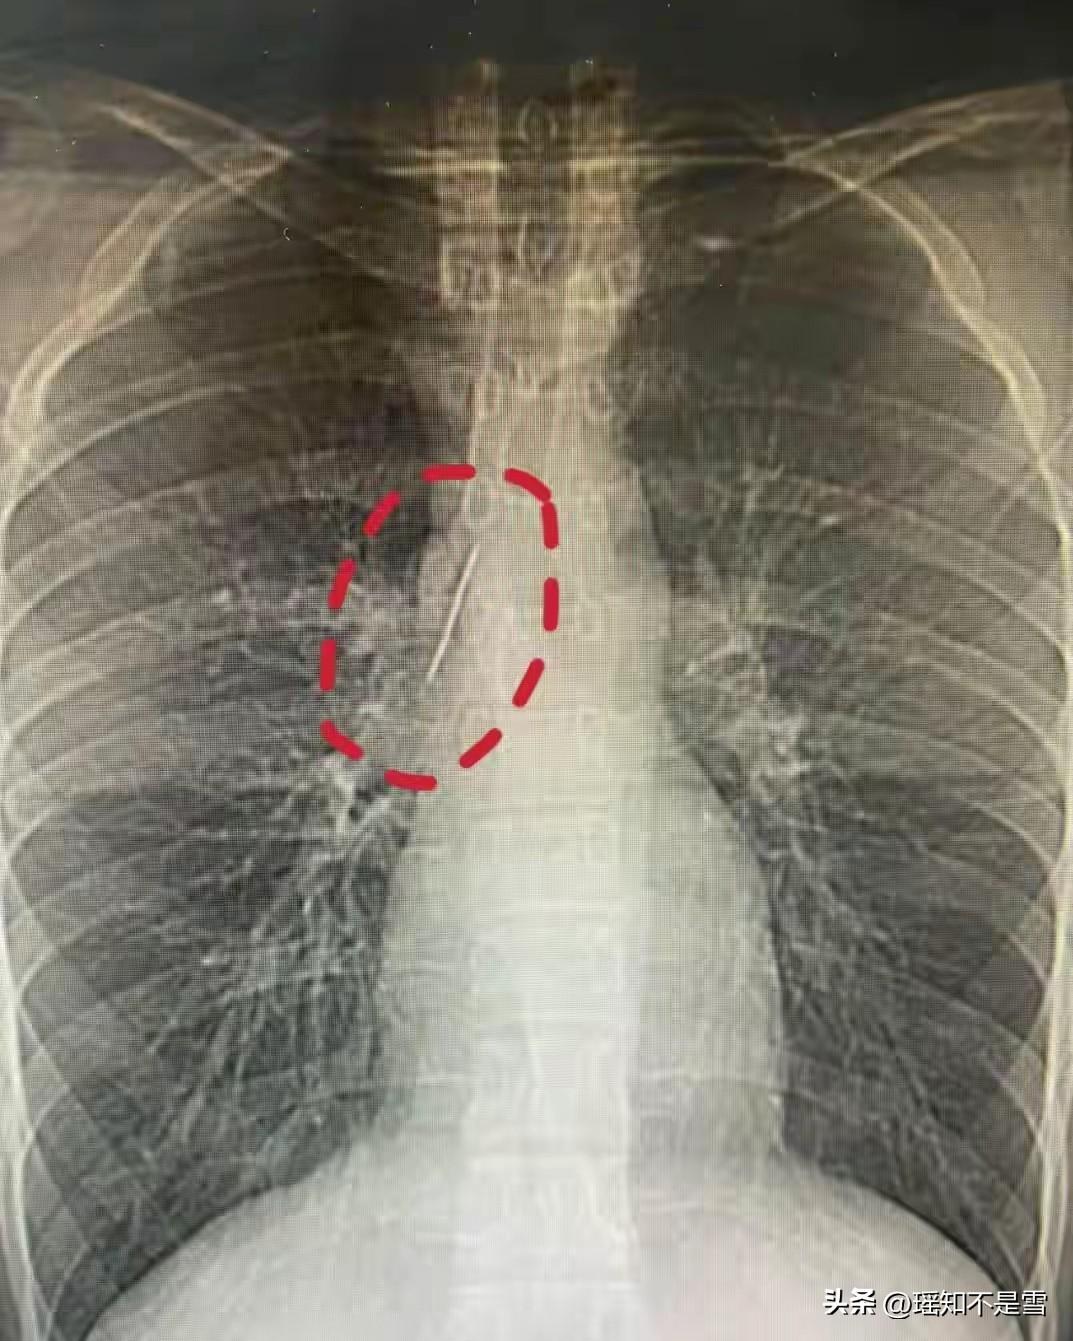

浙江一17岁小伙体检时发现胸腔藏了一根5厘米的缝衣针,医生:奇迹!紧贴大血管、刺入肺组织,十几年都没事。 这个小伙姓陆,我们就叫他小陆,家住浙江当地县城,今年刚满17岁,一直怀揣着军旅梦,这次体检正是为了报名参军做的准备。 他从小到大身体看着格外硬朗,平时跑操、打球、正常上学读书,从来没喊过胸口疼、胸闷,连感冒发烧都很少得,家人和他自己都觉得身体没任何问题,谁也没料到,一次常规的征兵胸片检查,会揪出这个埋藏了十几年的致命隐患。 拿到检查报告的那一刻,小陆和父母当场就懵了,看着片子里清晰的金属针影,一家人翻遍了记忆,也想不通这根针到底是怎么跑进胸腔里的。 医生看着检查结果,连呼不可思议,这根5厘米的缝衣针,斜着深深刺入了肺组织,针尖距离胸主动脉、上腔静脉这些核心大血管只有毫厘之差,几乎是紧紧贴在血管壁上。 要知道,胸腔里的大血管负责全身血液供应,管壁薄且压力大,哪怕是针尖轻轻蹭一下,都可能引发致命大出血,针体一旦移位刺破血管,人会在短时间内失去生命,就算是刺破肺组织,也会引发气胸、血胸,出现呼吸困难、休克等危险情况。 可小陆这十几年里,没有出现过任何相关症状,没有感染发炎,没有脏器损伤,针体就那样安稳地卡在脏器间隙里,这种情况在胸外科临床案例中极其少见,说他捡回了一条命,真的一点都不夸张。 后来在医生的反复提醒下,小陆父母才慢慢回忆起十几年前的往事。 那时候小陆才三四岁,正是对什么都好奇的年纪,家里长辈坐在床边缝补衣物,随手把缝衣针放在了床头,转身的功夫,小陆就抓着针玩了起来,没过多久就突然哇哇大哭,怎么哄都停不下来。 家人当时赶紧检查了他的全身,没看到明显的伤口,也没发现针的踪影,以为只是孩子调皮磕碰了一下,哭够了就没事了,压根没往针进入体内这方面想。 那时候孩子年纪小,表达能力差,没法说清自己的感受,加上针体刺入胸腔后,刚好避开了痛觉敏感的神经末梢,后续也没有触发急性症状,这根针就悄无声息地在他身体里待了十几年。 接诊的胸外科副主任冯兴医生,立刻意识到这个异物的危险性,它就像一颗定时炸弹,随时可能因为小陆的一个转身、一次深呼吸,甚至一次剧烈咳嗽,就发生移位。 医生团队马上安排了三维CT重建,精准锁定针体的位置和角度,反复推演手术方案,就怕术中碰到大血管引发意外。 手术采用的是微创手术,创口很小,但操作难度极高,医生全程屏住呼吸,一点点分离针体周围的组织,小心翼翼地避开要害血管,耗时一个多小时,才完整将这根缝衣针取了出来。 术后小陆恢复得很快,没过几天就顺利出院,军旅梦也终于能继续追寻,可这场有惊无险的经历,却给所有家长敲响了警钟。 我们总觉得意外离孩子很远,总觉得一些小疏忽不会造成大问题,可儿童的身体娇嫩,对危险毫无认知,缝衣针、纽扣电池、牙签、小零件这些日常物品,一旦被孩子误食或误入体内,初期症状往往很隐蔽,很容易被家长忽略。 很多家长和小陆的父母一样,孩子哭闹后只看表面有没有伤口,不会深究背后的原因,等到发现体内有异物时,往往已经埋下了长期的健康隐患。 小陆是幸运的,针体没有移位,没有造成不可逆的伤害,可这份幸运没法复制,不是每个孩子都能躲过这样的致命风险。 日常带娃时,家长一定要把尖锐、细小的危险物品收纳在孩子够不到的地方,别抱有任何侥幸心理。 孩子出现不明原因的哭闹、胸闷、咳嗽时,一定要多留个心眼,及时就医检查,别让一时的疏忽,变成伴随孩子十几年的隐患。 看似奇迹的平安,本质上是万千巧合凑成的侥幸,而我们能做的,就是杜绝侥幸,把安全防护做到极致。 各位读者你们怎么看?欢迎在评论区讨论。